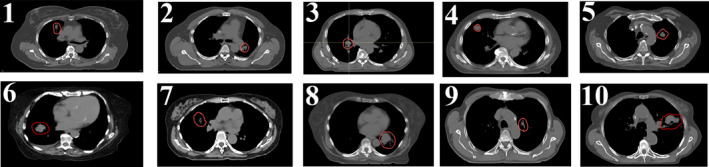

The location of the CTV in all ten patients is provided in Fig. 2. The dimension of the CTV ranged from 22.10 cc to 181.03 cc. The tumor motion ranged from 3.8 mm to 13.2 mm. The overall tumor motion was calculated from the magnitude of a 3D vector in the left–right (LR), anterior–posterior (AP), and superior–inferior (SI) directions.

FIG. 2.

The location of the CTV (red contour) in ten lung patients in the current study. The CTV ranged from 22.10 cc to 181.03 cc, whereas the tumor motion ranged from 3.8 mm to 13.2 mm